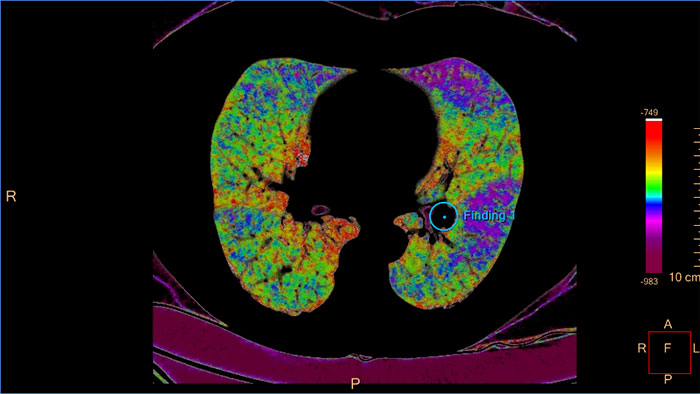

Review spectral data in a range of not spectral-enhanced CT applications

Allows retrospective use of spectral data that was saved in a series of spectral base images (SBI). The fast launch of LMG allows review and identification of the most relevant results to be launched into the application for further analysis.

IQon Spectral CT Functionality

IQon Spectral CT is the only scanner to offer CT Spectral Light Magic Glass and CT Spectral Magic Glass on PACS, helping radiologists review and analyze multiple layers of spectral data at once, including on their PACS.

IQon Spectral CT* Functionality

The spectral viewer is optimized for analysis of spectral data sets from the IQon Spectral CT Scanner. Obtain a comprehensive overview of each patient quickly and easily, quantify quickly, and assist in diagnosis. It is designed to accommodate general spectral viewing needs with additional tools to assist in CT images analysis.